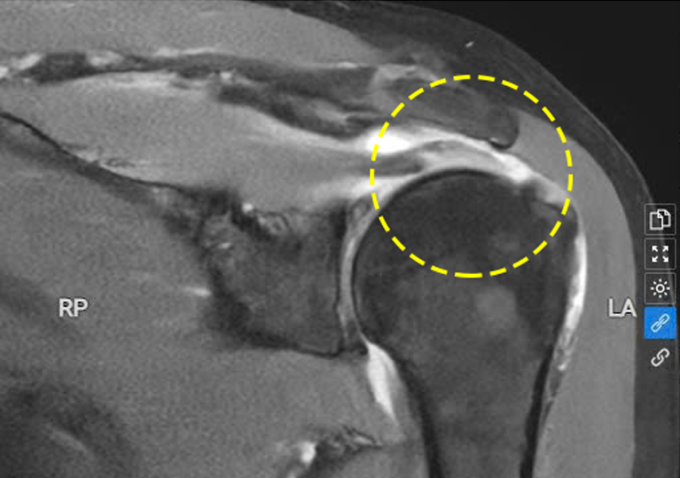

Phim chụp MRI cho thấy gân trên gai của bà Liên bị đứt. Ảnh: Bệnh viện Đa khoa Tâm Anh

BS.CKII Trần Tuấn Anh, khoa Chấn thương chỉnh hình, cho biết ảnh chụp X-quang khớp vai và cộng hưởng từ MRI phát hiện bà bị đứt gân cơ vai. Đây là một trong 4 cơ gắn với chóp xoay làm nhiệm vụ ổn định, kiểm soát chuyển động khớp vai. Bệnh nhân bị hẹp khoang dưới mỏm cùng vai, hai đầu xương vai và xương cánh tay quá sát nhau làm gân cơ chóp xoay bị chèn ép dẫn đến viêm, phát triển thành viêm bao hoạt dịch.